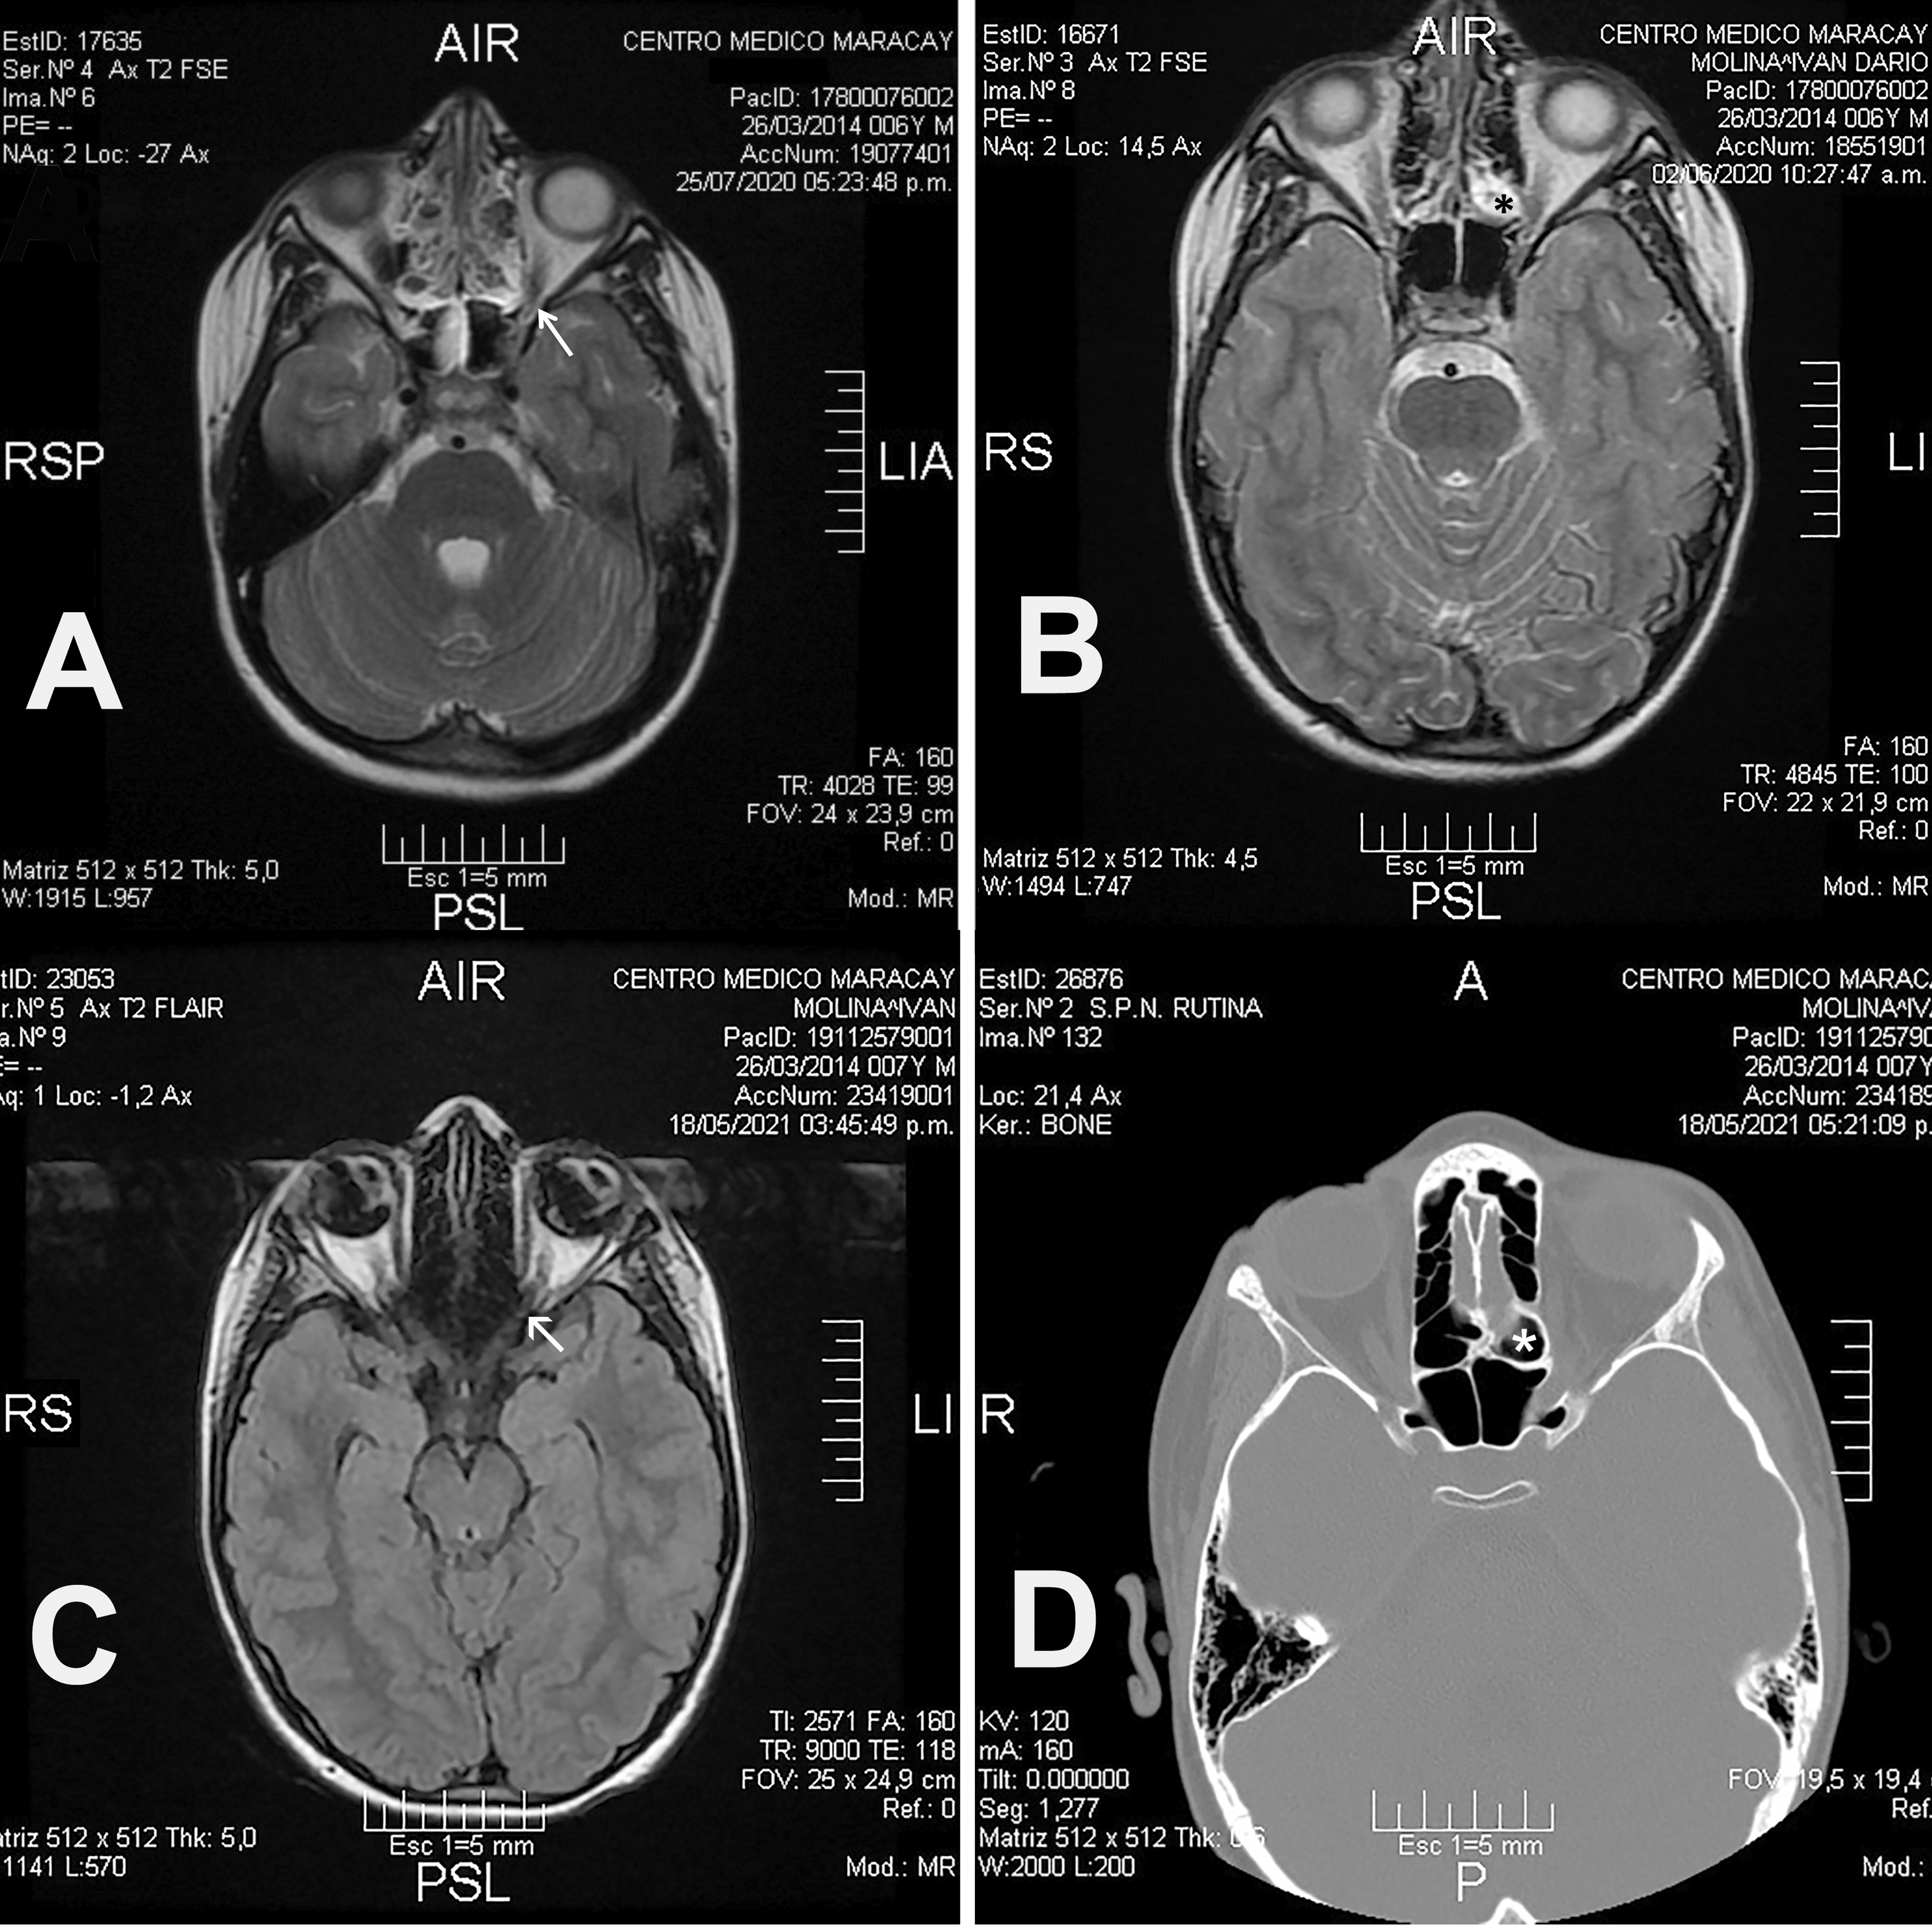

Remisión completa de Neuritis Óptica Retrobulbar ocasionada por sinusitis Etmoidal en un paciente pediátrico.

Aderito De Sousa Fontes, Maria Jose Zamora Santil

106-109